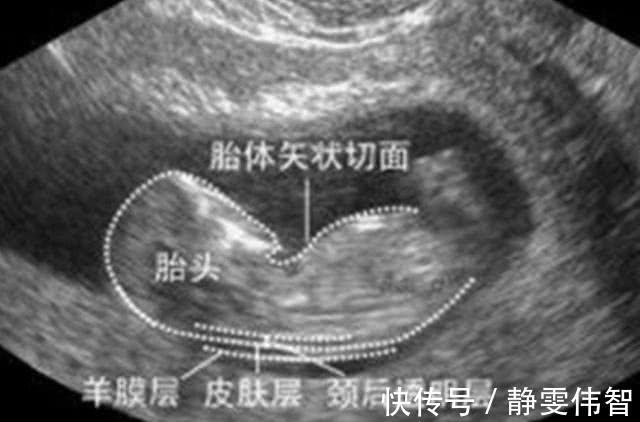

是nuchaltranslucency的简称,是指颈后透明层,即胎儿颈椎水平面皮肤到皮下软组织间的厚度。

它是目前一种通过B超手段来测量胎儿颈部皮下无回声透明层最厚部位的厚度,以此来评估胎宝宝是否患有唐氏综合征。

NT的正常厚度为2毫米内,再结合孕妈的年龄,若超出这个数值,就要引起重视,考虑胎儿是否存在唐氏综合征;